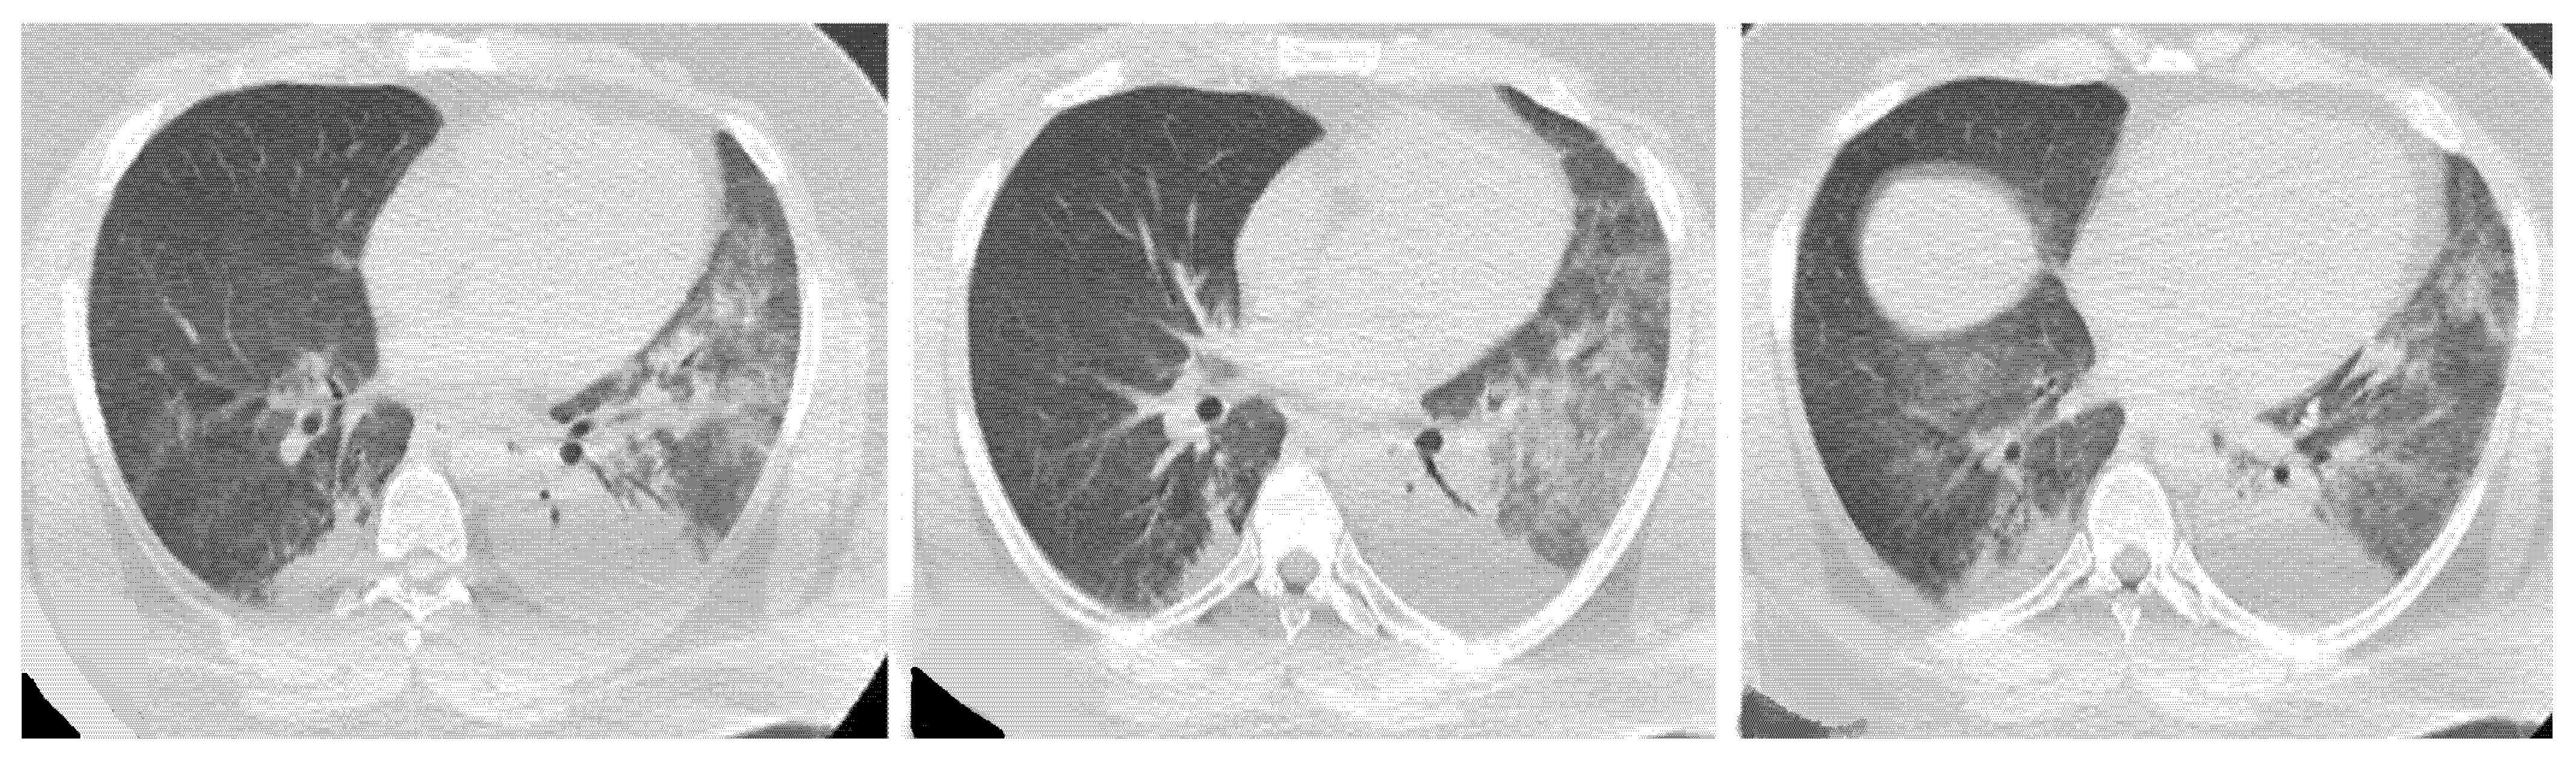

Acute Type